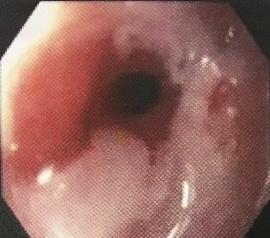

There is a spectrum of disorders ranging from the most common endoscopy-negative gastro-oesophageal reflux disease (GORD) to oesophageal mucosal damage, which can progress to ulceration and stricture formation, although only about 8% will have moderate or severe oesophagitis.

Esophageal stricture

© డా. గన్నవరపు నరసింహమూర్తి, CC0, via Wikimedia Commons